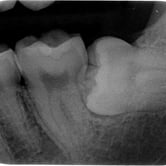

Extracción de Muelas del Juicio

La extracción de las muelas del juicio es un procedimiento quirúrgico para remover los terceros molares que pueden causar dolor, infección o daño a otros dientes debido a su posición o crecimiento anómalo.

Los pacientes pueden experimentar dolor, hinchazón y, en algunos casos, infección alrededor de estas muelas.

El tratamiento incluye la extracción quirúrgica para prevenir o resolver complicaciones.

Dientes impactados

Los dientes impactados son dientes que no pueden erupcionar correctamente debido a la falta de espacio o a una obstrucción.

Los pacientes pueden notar que un diente no ha salido, aunque debería haberlo hecho. Esta condición es común con las muelas del juicio y los caninos superiores.

El tratamiento puede incluir la extracción del diente impactado o la creación de espacio para permitir su erupción.